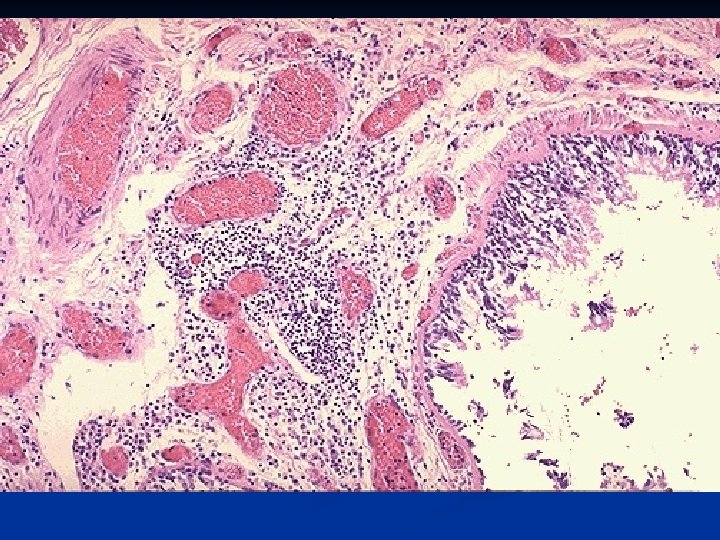

n Basic Mechanism - Bronchial plugging by thick mucous plugs containing eosinophils, whorls of shed epithelium (Curschmann’s spirals), and Charcot – Leyden crystals (Eosinophil membrane protein); - Distal air- spaces become over distended.

n Histology: -Thick basement membrane -Edema and infiltration of the bronchial walls by inflammatory cells with prominence eosinophils, - Hypertrophy of bronchial wall muscle. of